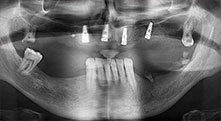

impianti

I quattro impianti sono fissati come programmato. I molari mascellari distali possono comunque essere utilizzati per fissare la protesi in linea introdotta un mese dopo l'impianto.